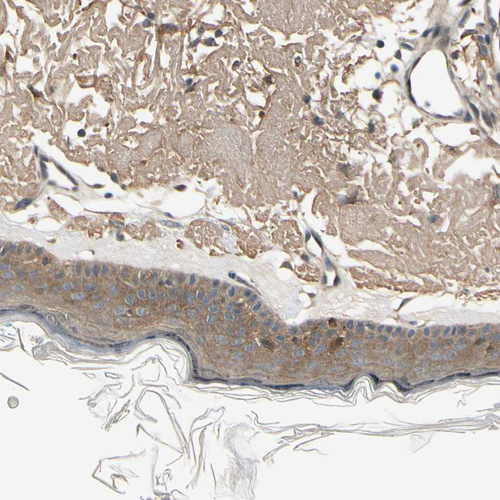

Immunohistochemistry analysis in human skin and skeletal muscle tissues using HPA008184 antibody. Corresponding EPHB3 RNA-seq data are presented for the same tissues.